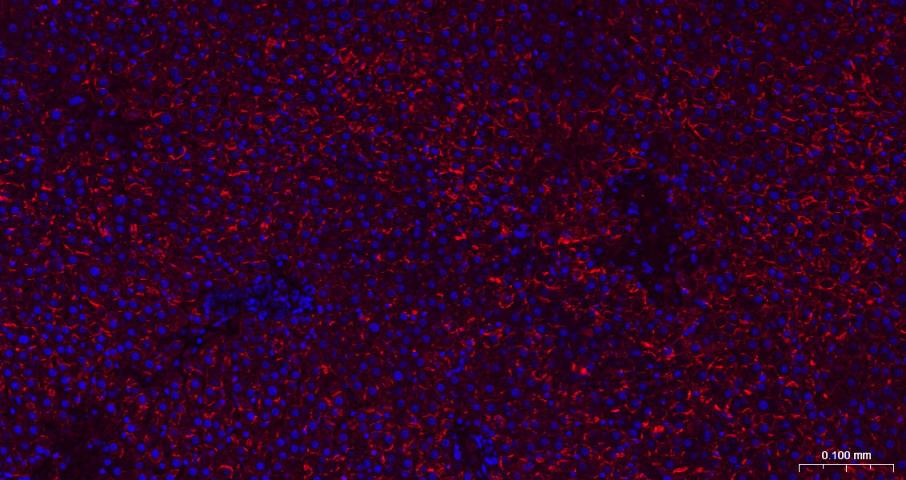

Paraformaldehyde-fixed, paraffin embedded Human Liver; Antigen retrieval by boiling in sodium citrate buffer (pH6.0) for 15 min; The section was incubated with N Cadherin Monoclonal Antibody, Unconjugated (bsm-52389R) at 1:200 overnight at 4°C. Followed by conjugated Goat Anti-Rabbit IgG antibody (Red, bs-0295G-BF594), DAPI (blue, C02-04002) was used to stain the cell nuclei.